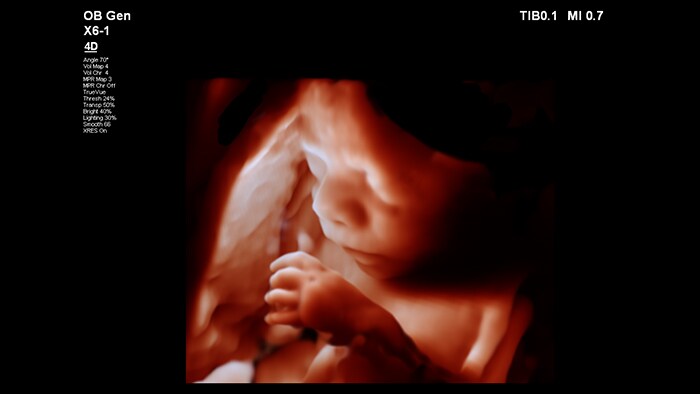

En este vídeo, el Dr. Michael Ruma presenta el transductor V9-2 para ultrasonidos 3D de Philips. El V9-2 es el primer transductor mecánico PureWave para ultrasonidos 3D de la división de ultrasonidos de Philips específico para obstetricia/ginecología y ofrece una extraordinaria calidad de imagen y un diseño ergonómico avanzado. El V9-2 está especialmente indicado para la adquisición de imágenes 2D, 3D y 4D para exploraciones obstétricas del primer, segundo y tercer trimestre.

Combinar el nuevo transductor V9-2 con el sistema de ultrasonidos de alta gama EPIQ Elite ofrece una adquisición de imágenes superior de obstetricia/ginecología:

Herramientas de visualización obstétrica avanzadas para una imagen fetal realista.